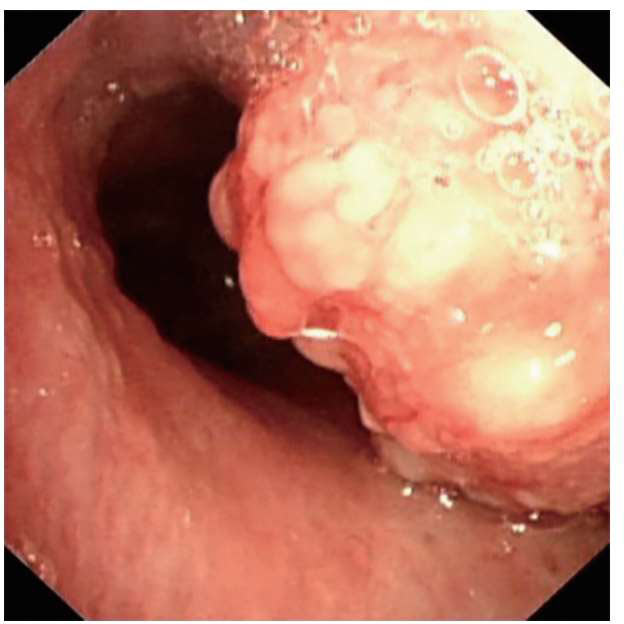

1.高风险人群: 对于肺癌高风险群体,如长期吸烟者、有家族肺癌史者、长期接触职业粉尘者等,医生会建议行胸部CT检查作为早期筛查手段。某些肺癌早期可能没有明显症状,而CT可以直接发现肺部微小的异常变化,可以发现新出现的肺结节或纵隔异常。当肺部结节增大时,可能出现压迫支气管,导致支气管狭窄。如果临床高度怀疑肺癌,医生常常会建议患者做支气管镜检查,可以在支气管镜下发现气管肿瘤病变,这样有助于早诊早治,大大提高治愈率。

支气管镜下发现气管肿瘤病变